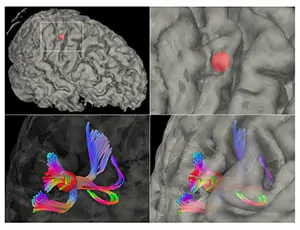

今回は、4月26日に英国科学誌『Cerebral Cortex』に掲載された論文、”Pyramid-Shape Crossings and Intercrossing Fibers Are Key Elements fo … 続きを読む プレス情報-脳機能の根幹に関わる脳表層の微小構造を発見!